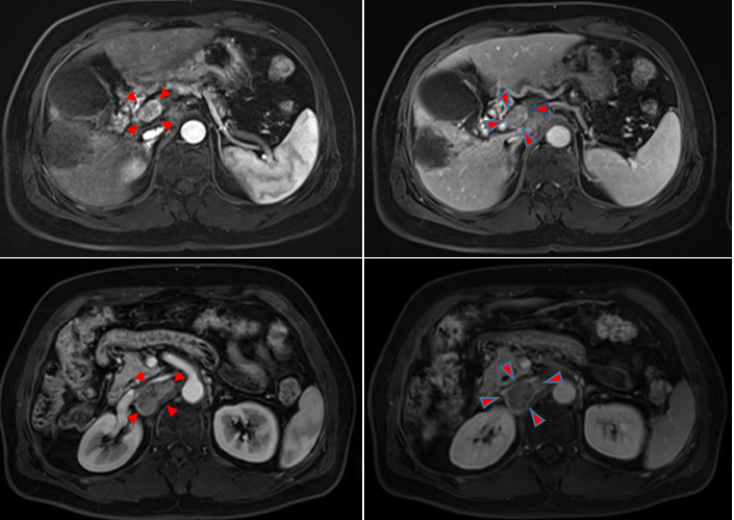

2020年12月6日复查MRI,提示门脉右支出现癌栓(VP4)。整体评效疾病进展(PD);腹膜后淋巴结呈稳定状态(图3)。

图3.2020年12月6日复查MRI

2021年1月18日复查上腹部MRI示,肝内病灶无明显活性,门脉右支癌栓部分消退,腹膜后淋巴结仍为稳定状态,总体评价PR(图5)。

图5.2021年1月18日复查上腹部MRI